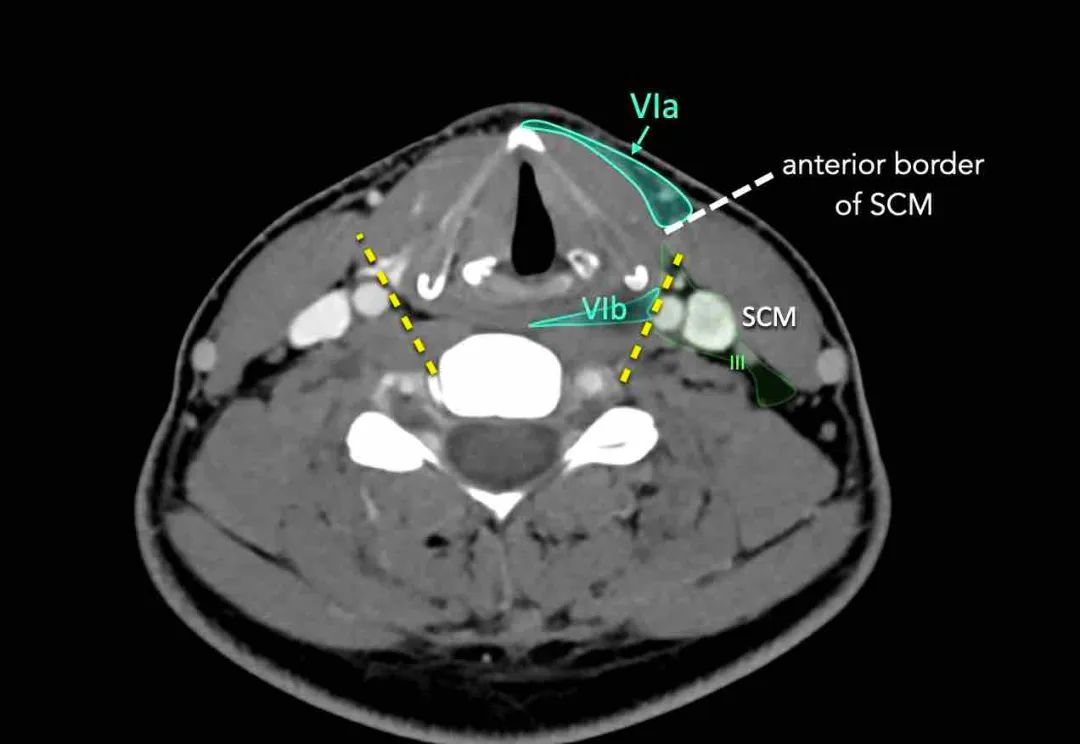

这一层包括浅表的颈前淋巴结(VIa层)和较深的喉前、气管前、气管旁和喉返神经淋巴结(VIb层)。

VIa

这一层包含表浅的颈前淋巴结。

VIb

该水平包含在颈总动脉的内侧边界之间。

该区域中的节点有: